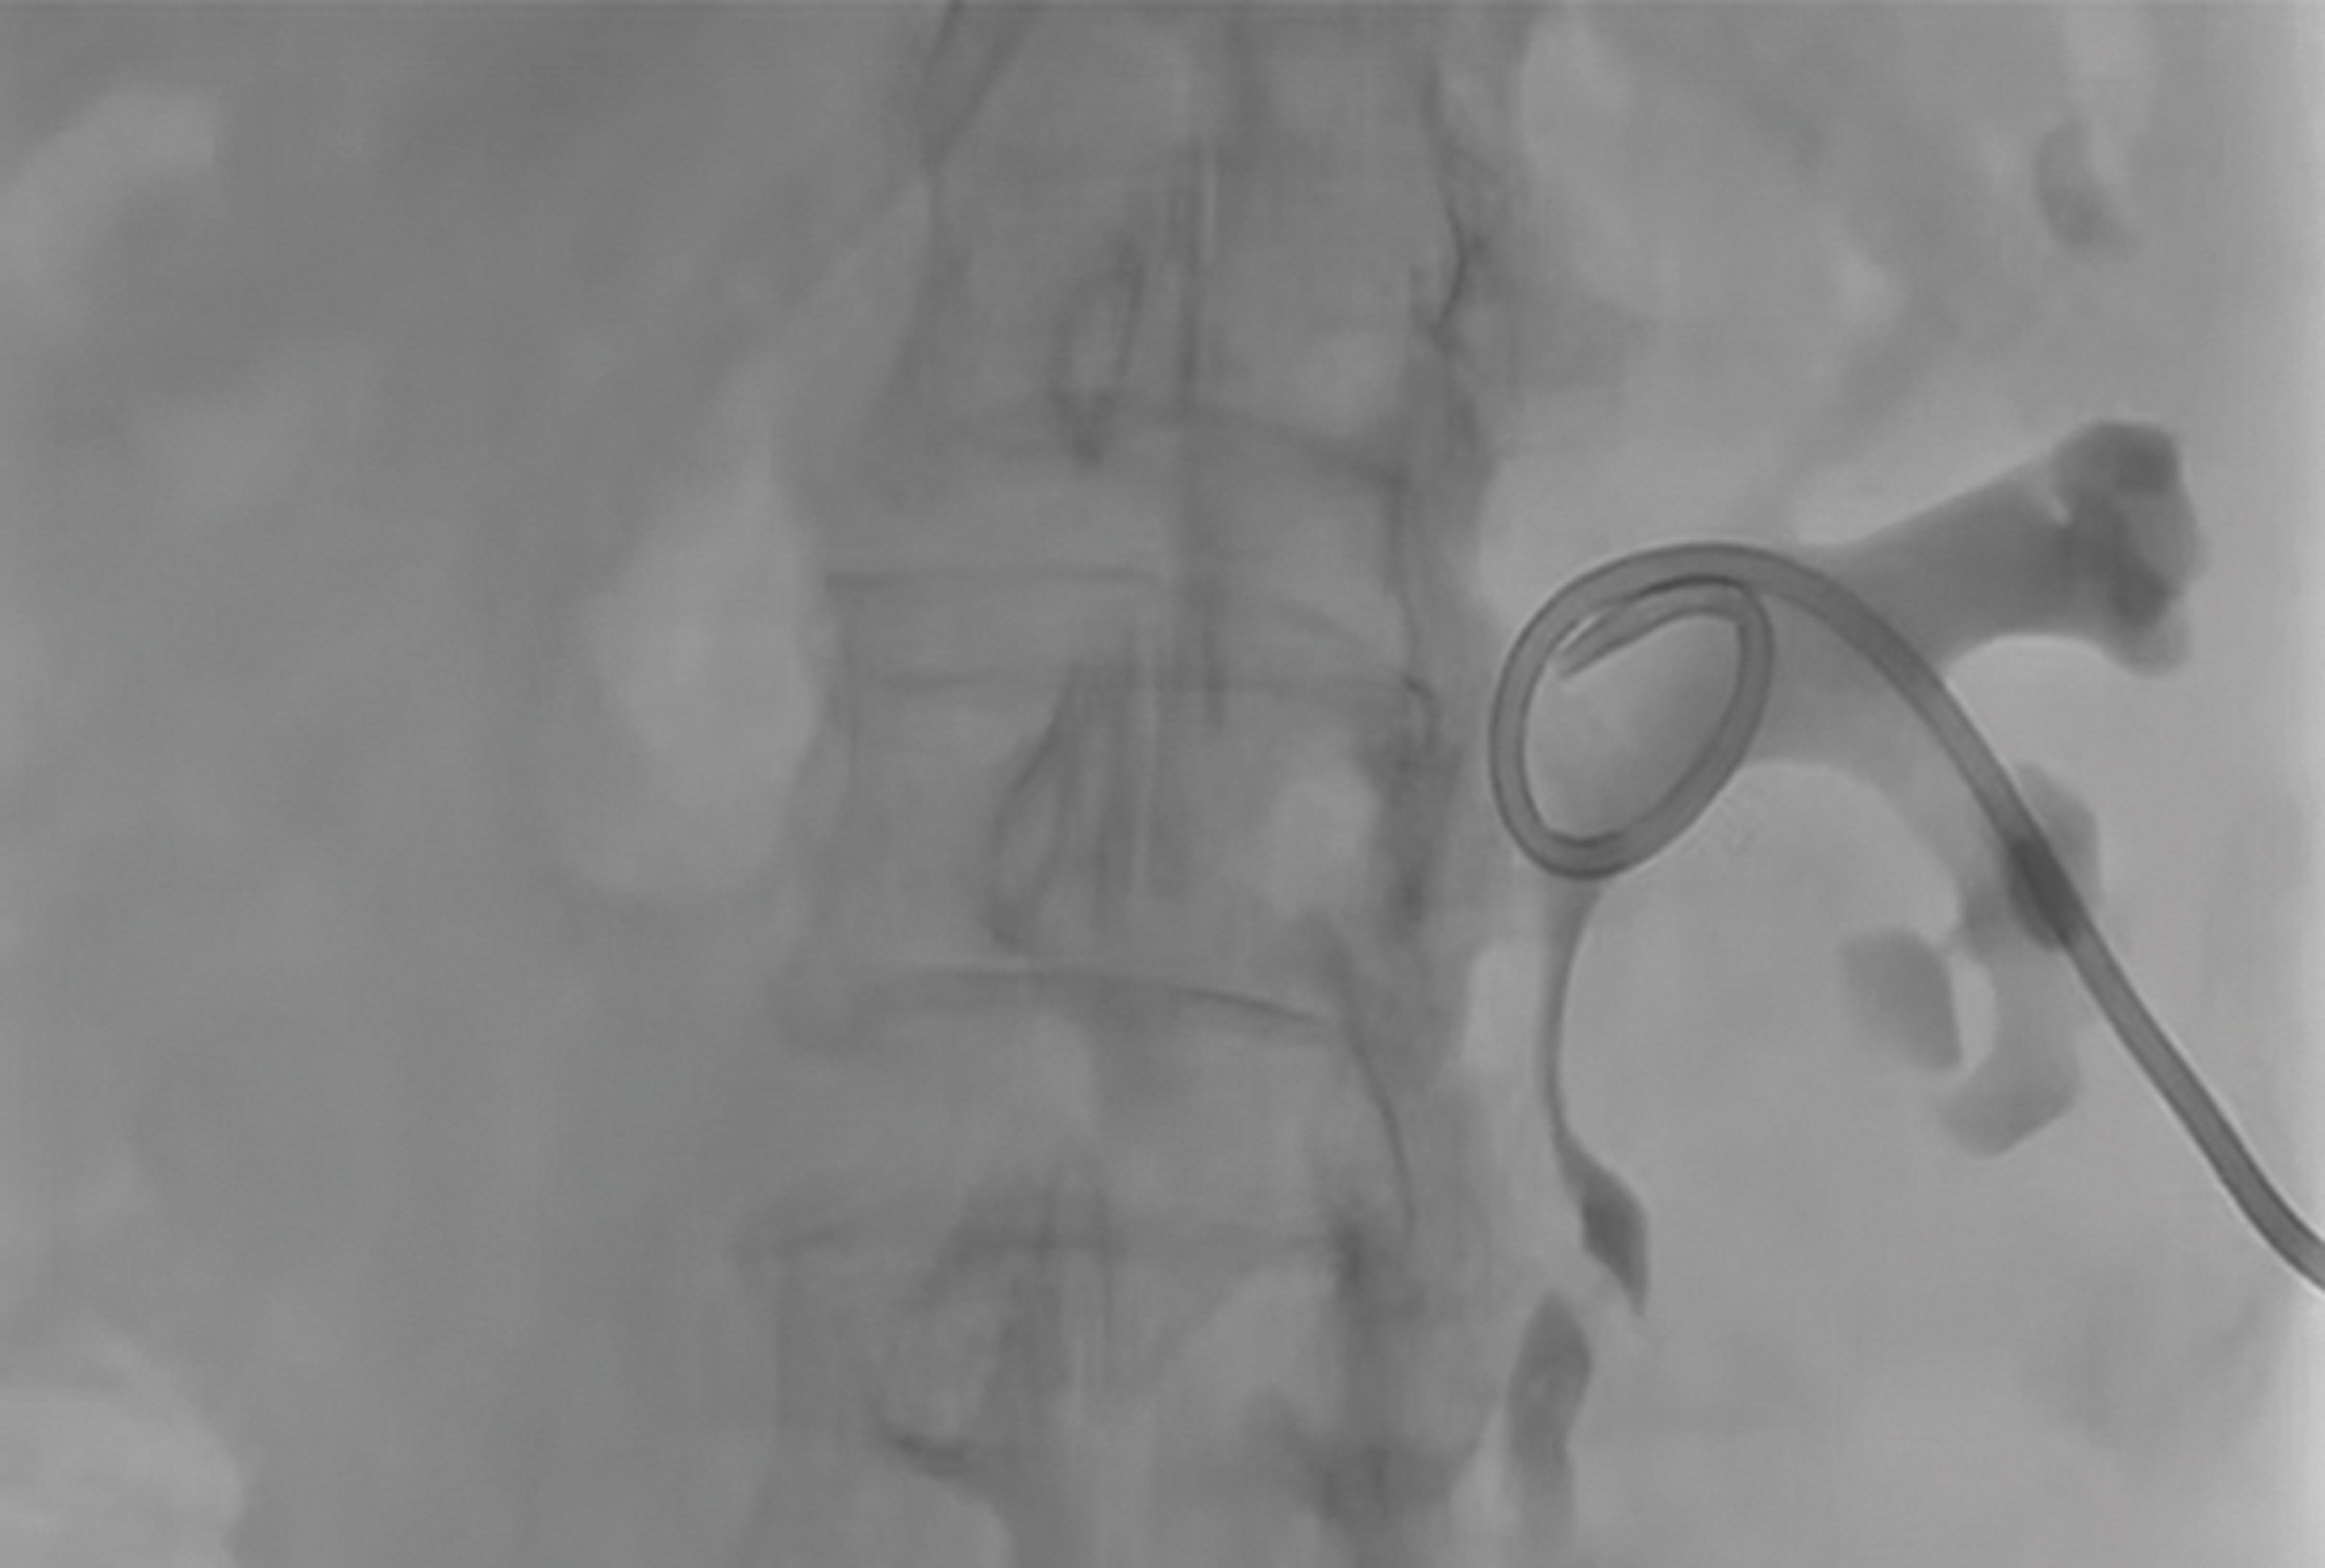

Figure 3.

- Describe Figure 3. What are the contraindications to and possible complications of percutaneous nephrostomy insertion?

4. Figure 3 shows a fluoroscopic image of a left percutaneous nephrostomy tube. There are no absolute contraindications to PCN insertion. Relative contraindications include:

- Uncorrected bleeding diathesis / coagulopathy.

- Severe electrolyte abnormalities (K+ >7) or metabolic acidosis; whilst nephrostomy insertion is ultimately required to correct these abnormalities, these patients should undergo medical optimisation, which may include haemodialysis / filtration prior to nephrostomy insertion.

- Uncontrolled hypertension.

- Uncooperative patient [3].

Below is a list of possible complications that should be included in consenting for PCN insertion:

- Severe bleeding.

- Vascular injury requiring embolisation or nephrectomy.

- Damage to adjacent structures; liver, bowel, spleen.

- Urine leak / urinoma.

- Pneumothorax.

- Worsening sepsis.

- Failed insertion.

- Tube displacement / blockage [3].